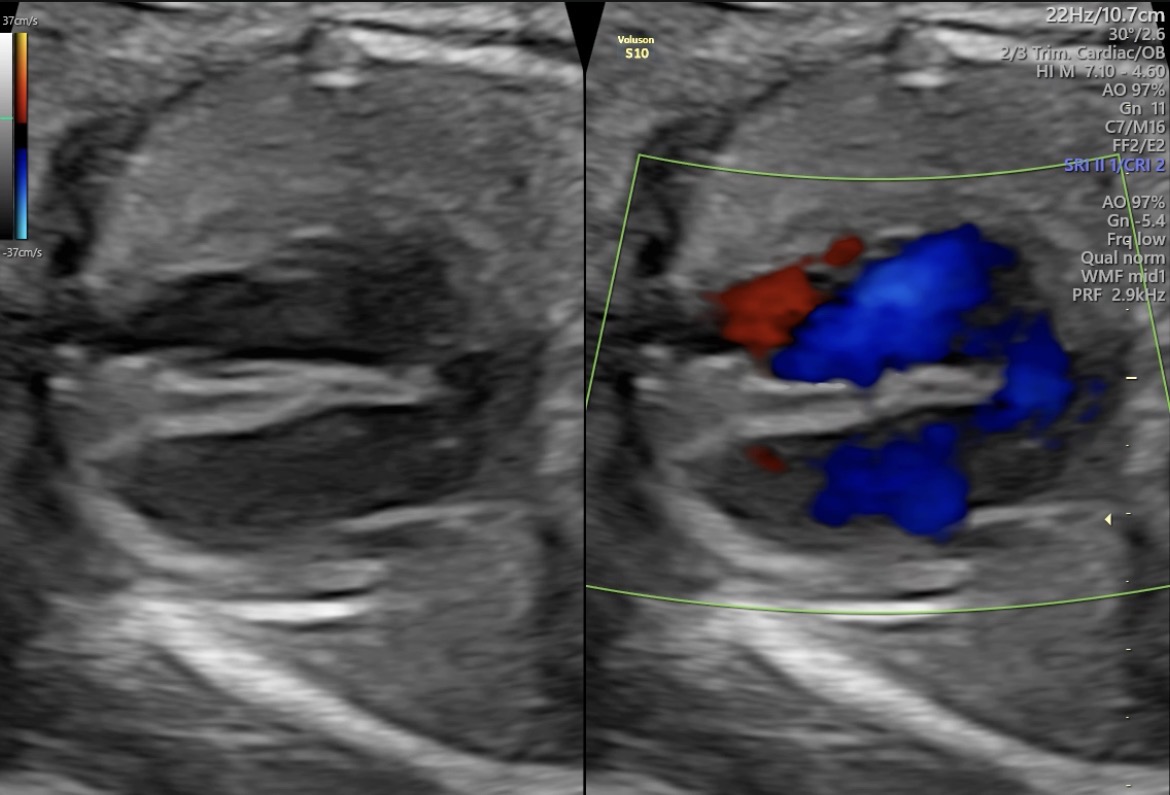

Ecocardiografía Fetal

Evaluación minuciosa y especializada de la estructura y función del corazón fetal, fundamental para detectar cardiopatías congénitas antes del nacimiento.